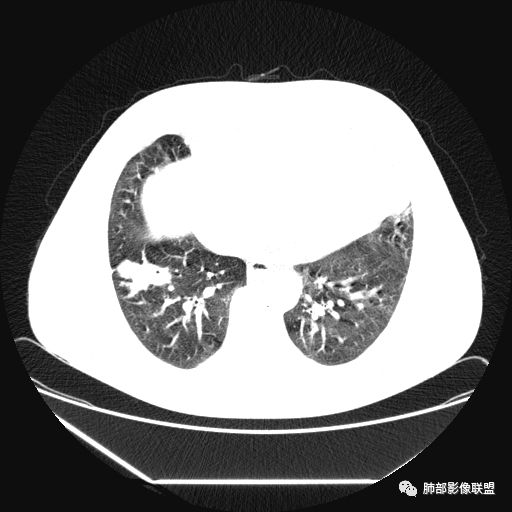

曹志勇:右肺尖后段类圆形病灶,边界清边,缘锐利,宽基底与胸膜相连,环形强化,内似见蛇纹血管征,考虑胸膜孤立性纤维瘤,右肺外底段病灶,考虑炎性可能大

红日东升:左侧胸椎旁肿块,边缘清晰光整,冠状位见D字征,未见支气管进入,肺组织受压表现,定位肺外。轻度强化,密度稍不均匀,临近肋骨变细,未见肺动脉供血,考虑良性肿瘤,神经源性可能。右肺下叶病灶,轻度强化,血管显影,边缘平直、凹陷,考虑炎性病变。

张帅:患者中年男性,咳嗽 咳痰3月,痰为白色粘痰,左上肺病灶,边缘光滑,周围未见毛刺 分叶,肺组织受挤压,与胸膜关系密切,部分层面与胸膜脂肪间隙消失,有胸膜尾征,病灶定位于胸膜,病灶增强可见强化,边缘可见增强血管,内可见低密度区,考虑 孤立胸膜纤维瘤?神经鞘瘤?右肺下叶外基底段病灶,病灶与胸膜有牵拉,病灶边缘光滑,平直 u型征,未见明显毛刺,增强病灶内可见增强血管影,边缘低密度,考虑病灶内存在痰栓。右下肺病灶考虑良性炎症性病灶,ABPA?

张立:左侧胸椎旁肿块,边缘清晰光整,冠状位见D字征,未见支气管进入,肺组织受压表现,定位肺外。轻度强化,密度稍不均匀,,未见肺动脉供血,神经源性肿瘤,节细胞神经瘤可能。右肺下叶病灶,轻度强化,血管显影,边缘平直、凹陷,TB可能。

可芸:定位:肺外病变,胸椎旁肿块,边缘清晰光整,可见胸膜尾征无支气管进入,肺组织受压。轻度强化,密度稍不均匀,未见肺动脉供血,考虑良性肿瘤,神经源性,孤立性纤维瘤?右肺下叶病灶,轻度强化,血管显影,边缘平直、凹陷,炎性病变。

1.左上胸内脊柱旁半圆形肿块,质地坚实,密度比较均匀。

2.病灶周边见胸膜掀起,应当考虑胸壁或是纵隔来源,肺内病变不会如此。